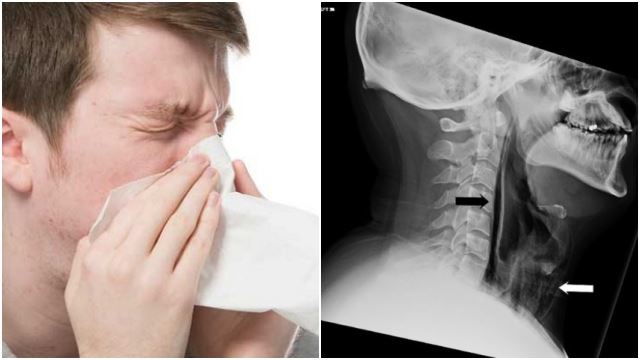

Saluran Darah Otak Boleh Pecah Sekiranya Korang Tahan Bersin

Bersin Sambil Tutup Hidung Boleh Buatkan Luka Dalaman